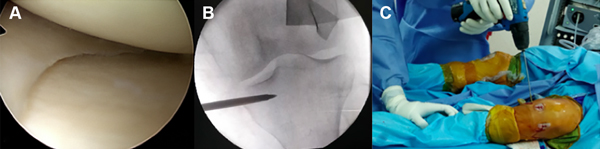

Luego del aspirado de médula ósea se realiza una artroscopía exploradora de la rodilla izquierda. Se observó una rodilla sin compromiso del cartílago y ambos meniscos sin lesión (fig. 6A). Posteriormente, bajo guía radioscópica (fig. 6B) se efectuaron perforaciones descompresivas tipo forage con mecha de 3.2 mm en platillo tibial (fig. 6C) y se colocaron 2 ml de concentrado de médula ósea.

Figura 6: Rodilla izquierda. A) Imagen intraoperatoria artroscópica. Meseta tibial interna (debajo), cuerpo del menisco interno y cóndilo femoral interno sin alteraciones. B) Control con radioscopia previa descompresión. C) Perforación-descompresión con mecha de 3.2 mm en platillo tibial.

En la evaluación artroscópica de la rodilla derecha se observó una lesión osteocondral extensa en el cóndilo femoral interno de aproximadamente 4 cm2 (fig. 7A). A pesar de que por la superficie de la lesión una opción viable era un trasplante osteocondral, se decidió extraer el fragmento (fig. 7B), realizar microperforaciones al lecho de la lesión y se colocar 2 ml de aspirado de médula ósea concentrado intraarticular y 2 ml en lecho lesional a través del portal artroscópico (fig. 7C).

Figura 7: Rodilla derecha. A) Imagen artroscópica en la que se evidencia la lesión osteocondral extensa en el cóndilo femoral interno. B) Pieza quirúrgica resecada, de aproximadamente 4 cm2. C) Colocación de aspirado de concentrado de médula ósea por el portal artroscópico.